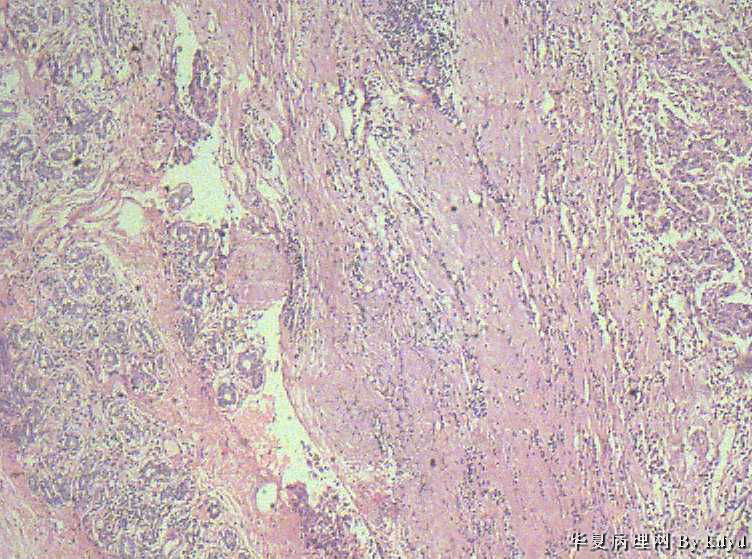

B3997左乳肿瘤--浸润性导管癌?

37岁,女。左侧乳腺肿块发现5个多月,伴隐痛。

手术见:肿块与周围组织分界不清,无明显包膜。

大体:不整形组织大小约3.5*35*2CM,未见明显包膜。质较软,切面浅黄色,一侧见一小囊腔直径约0.8CM囊壁较粗糙。

• 左乳肿瘤--浸润性导管癌?图1

图1

标签:乳腺浸润性导管癌 原位癌

浸润性乳腺导管癌?

IDC

乳腺浸润性导管癌

囊壁内大量炎细胞浸润,囊壁被覆细胞有明显异型,可见核分裂,考虑癌,不知有无陷阱

浸润性导管癌

应该是个浸润性导管癌

但是,片子质量欠佳

不太敢直接下